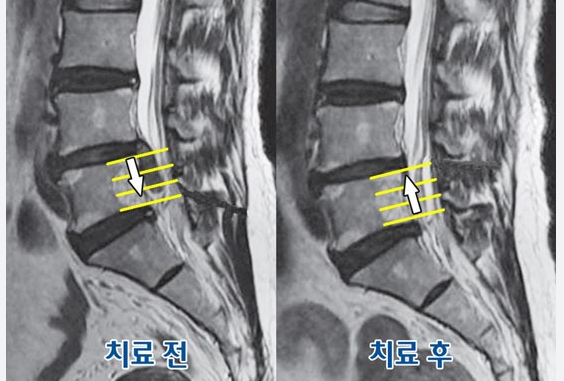

다행히 대부분의 경우 수술 없이 약물치료, 물리치료, 도수치료, 자세 교정 등으로 호전됩니다.